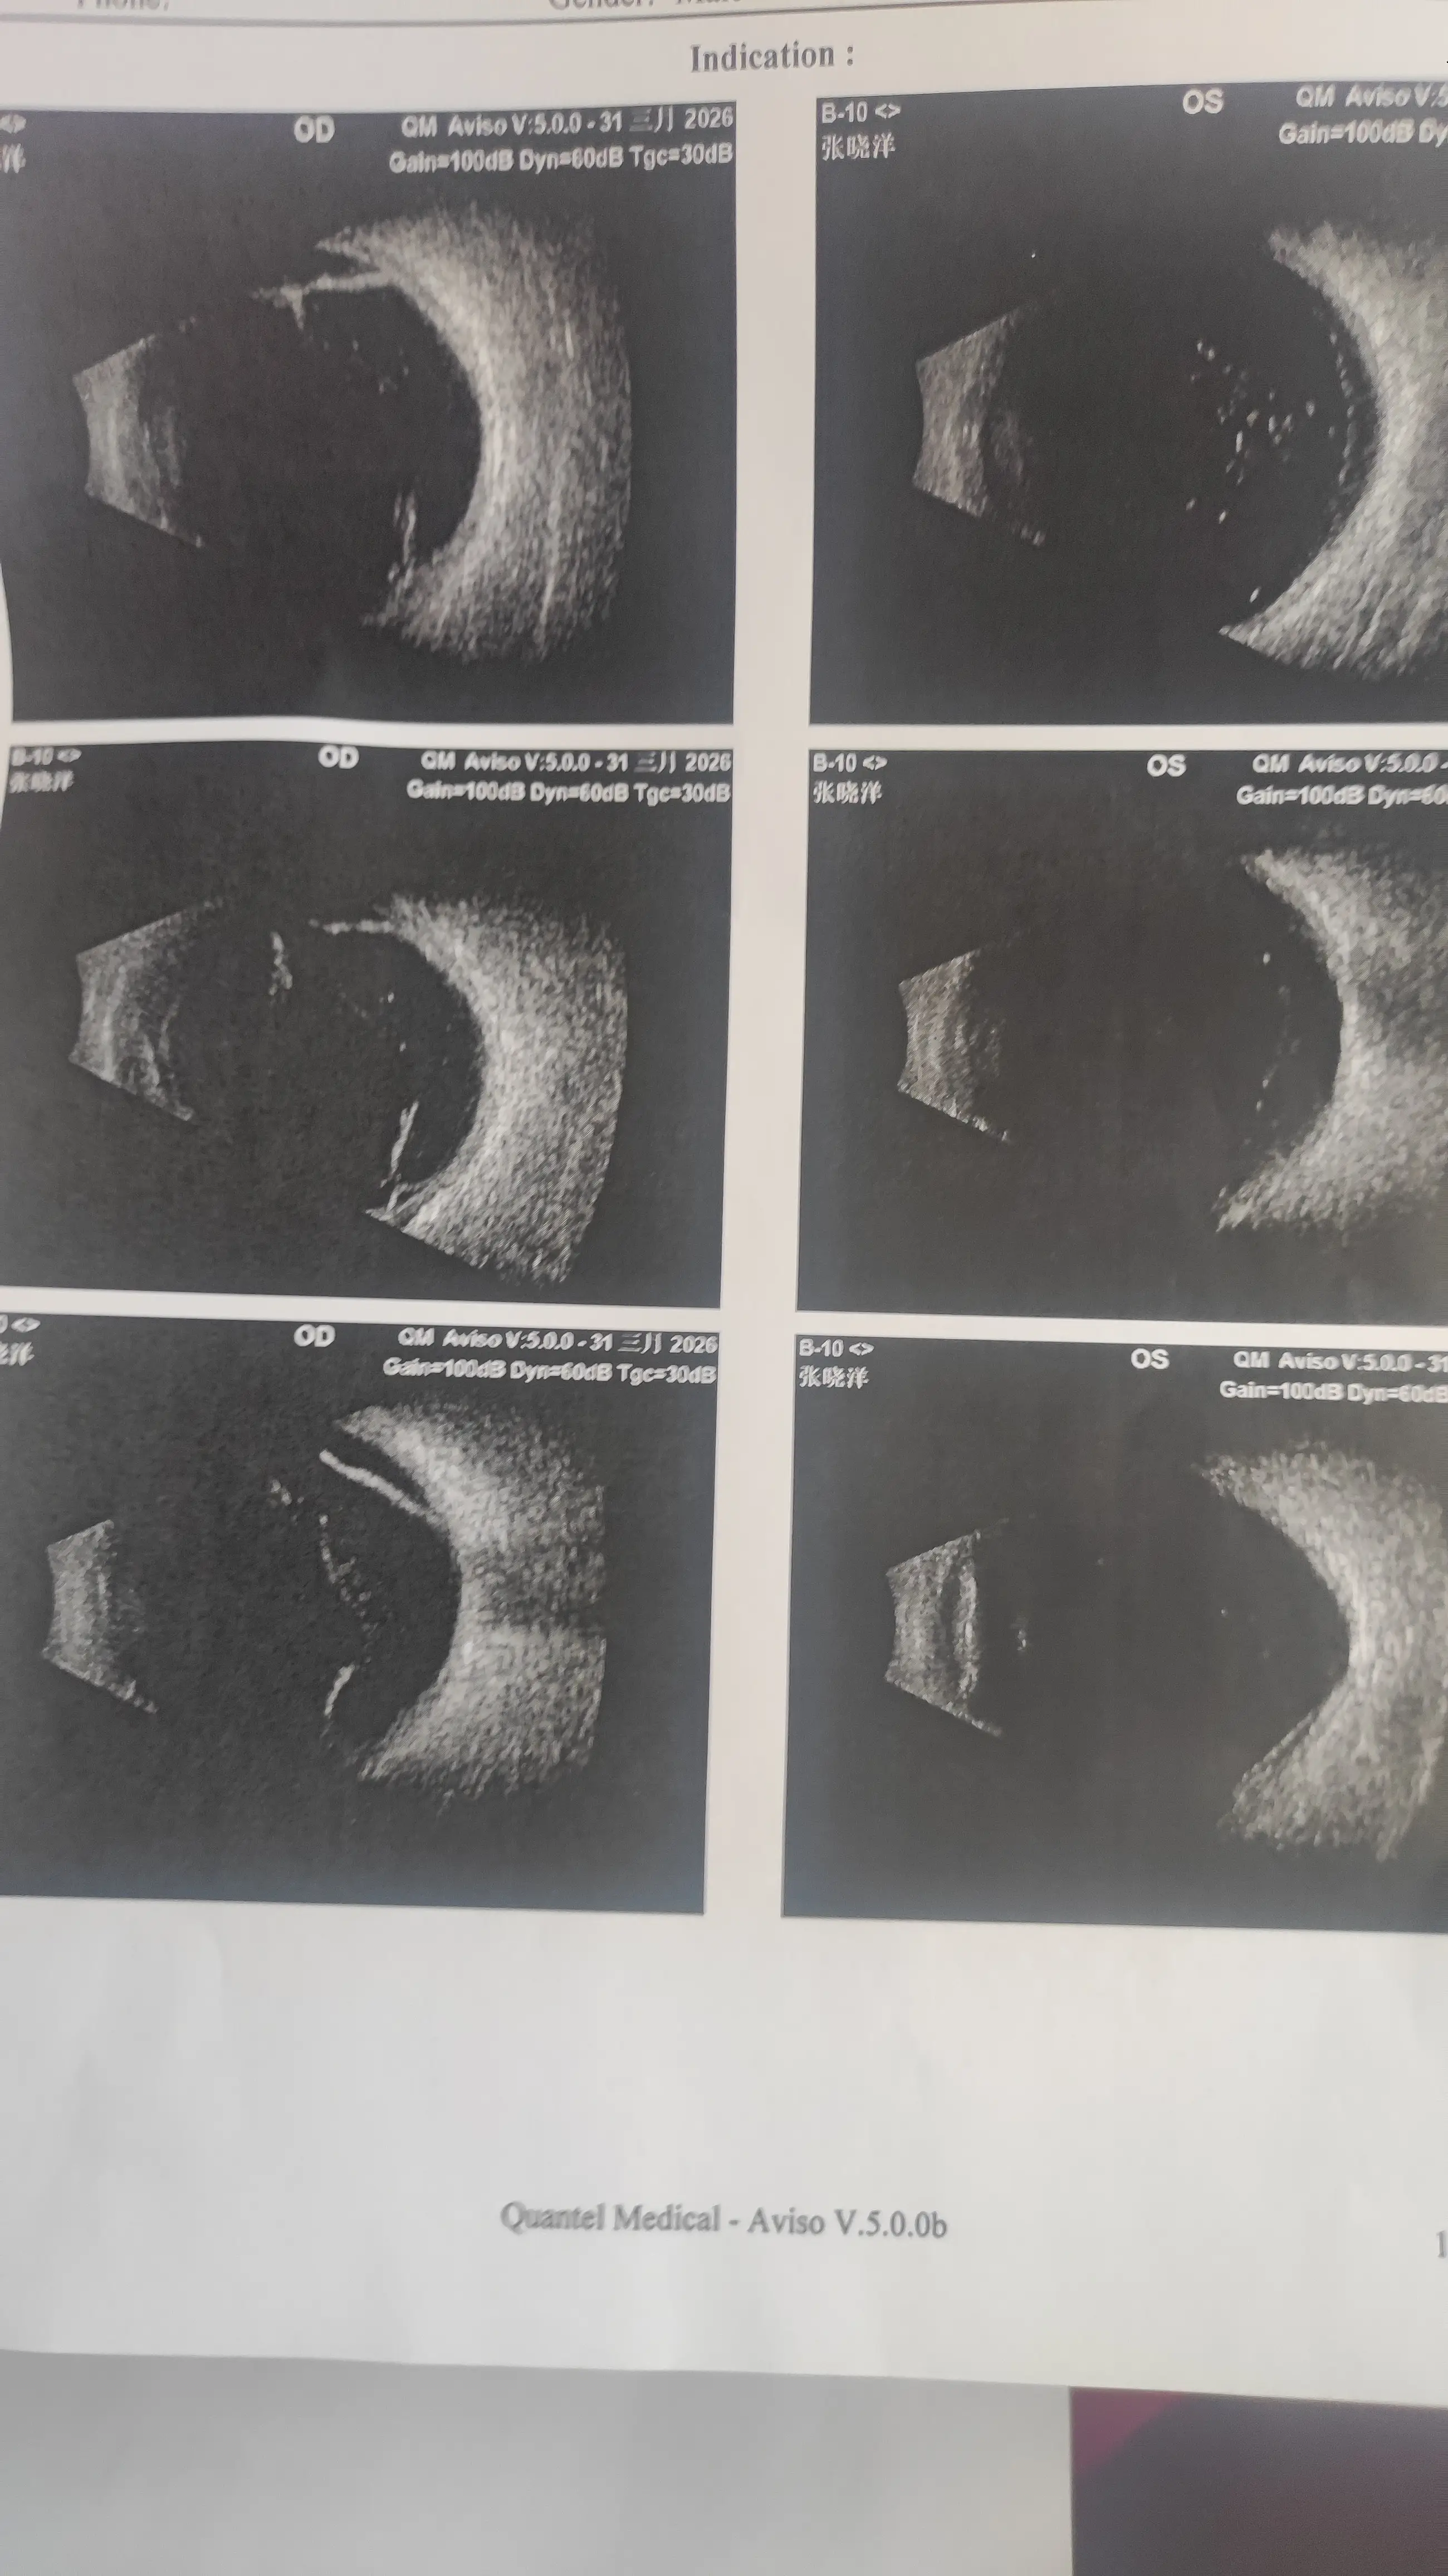

然后就喜提了一个坏消息:视网膜脱落。

希望你们都能好好的,如果有和站长一样,高度近视的,一定要定期去医院检查一下眼底。

提前发现的话,不仅治疗简单,花费也少。

最后,给大家看一下病例吧,以示警戒,希望大家关爱用眼健康!